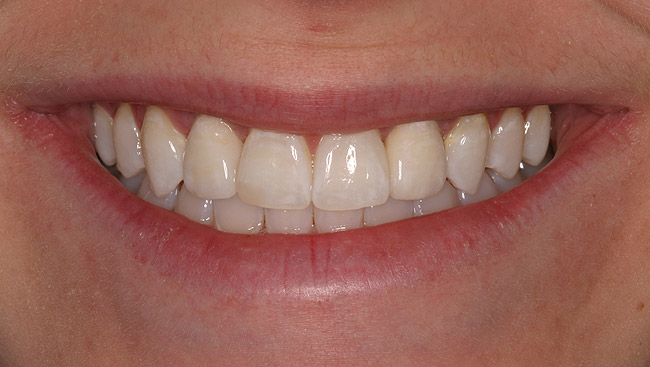

Figure 6d Completed treatment: revised RCT, zirconium post/pressed ceramic core cemented with Panavia 21¬Æ Resin Cement (Kuraray Dental). All-ceramic full-coverage crown cemented with Kerr NX3 Nexus¬Æ Third Generation Dual Cure Resin cement. Implant therapy not indicated.

Figure 6d

Figure 6e  Completed treatment: revised RCT, zirconium post/pressed ceramic core cemented with Panavia 21¬Æ Resin Cement (Kuraray Dental). All-ceramic full-coverage crown cemented with Kerr NX3 Nexus¬Æ Third Generation Dual Cure Resin cement. Implant therapy not indicated.

Figure 6e

Figure 6f  Completed treatment: revised RCT, zirconium post/pressed ceramic core cemented with Panavia 21¬Æ Resin Cement (Kuraray Dental). All-ceramic full-coverage crown cemented with Kerr NX3 Nexus¬Æ Third Generation Dual Cure Resin cement. Implant therapy not indicated.

Figure 6f